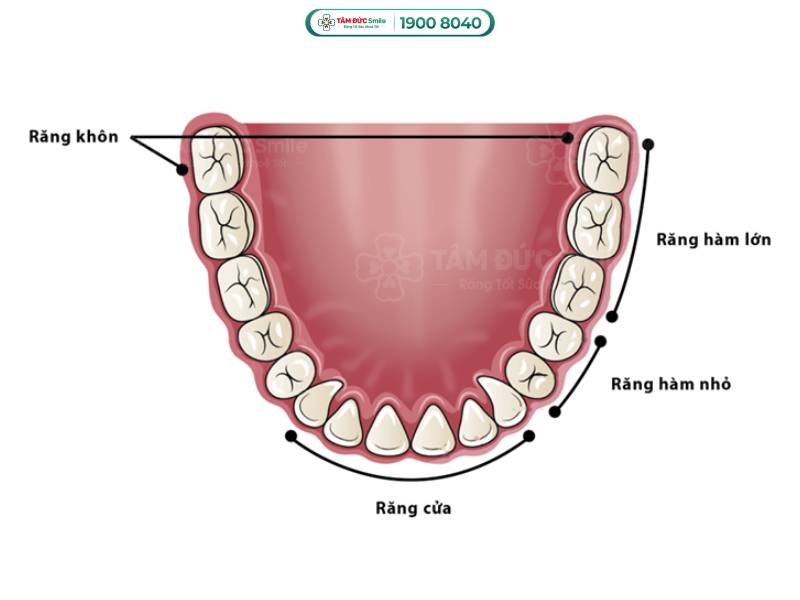

Răng khôn có cấu tạo tương tự như răng hàm với bề mặt nhai nhiều gờ và rãnh. Chúng ta mọc răng khôn ở độ tuổi trưởng thành, từ 17 - 25 tuổi. Theo đánh giá của chuyên gia nha khoa, nhổ răng khôn nguy hiểm bởi 5 lý do chính sau đây.

Vị trí và hình dáng của răng khôn

1.2. Răng khôn nằm ở vị trí khuất trong cung hàm

Tính từ ngoài vào trong, răng khôn nằm ở vị trí số 8 trong cùng của hàm. Vị trí này gây khó khăn cho bác sĩ khi phải đưa các dụng cụ nha khoa vào trong như tay khoan, mũi khoan, kìm nhổ răng,...

Răng khôn nằm ở vị trí số 8 trong cùng của hàm